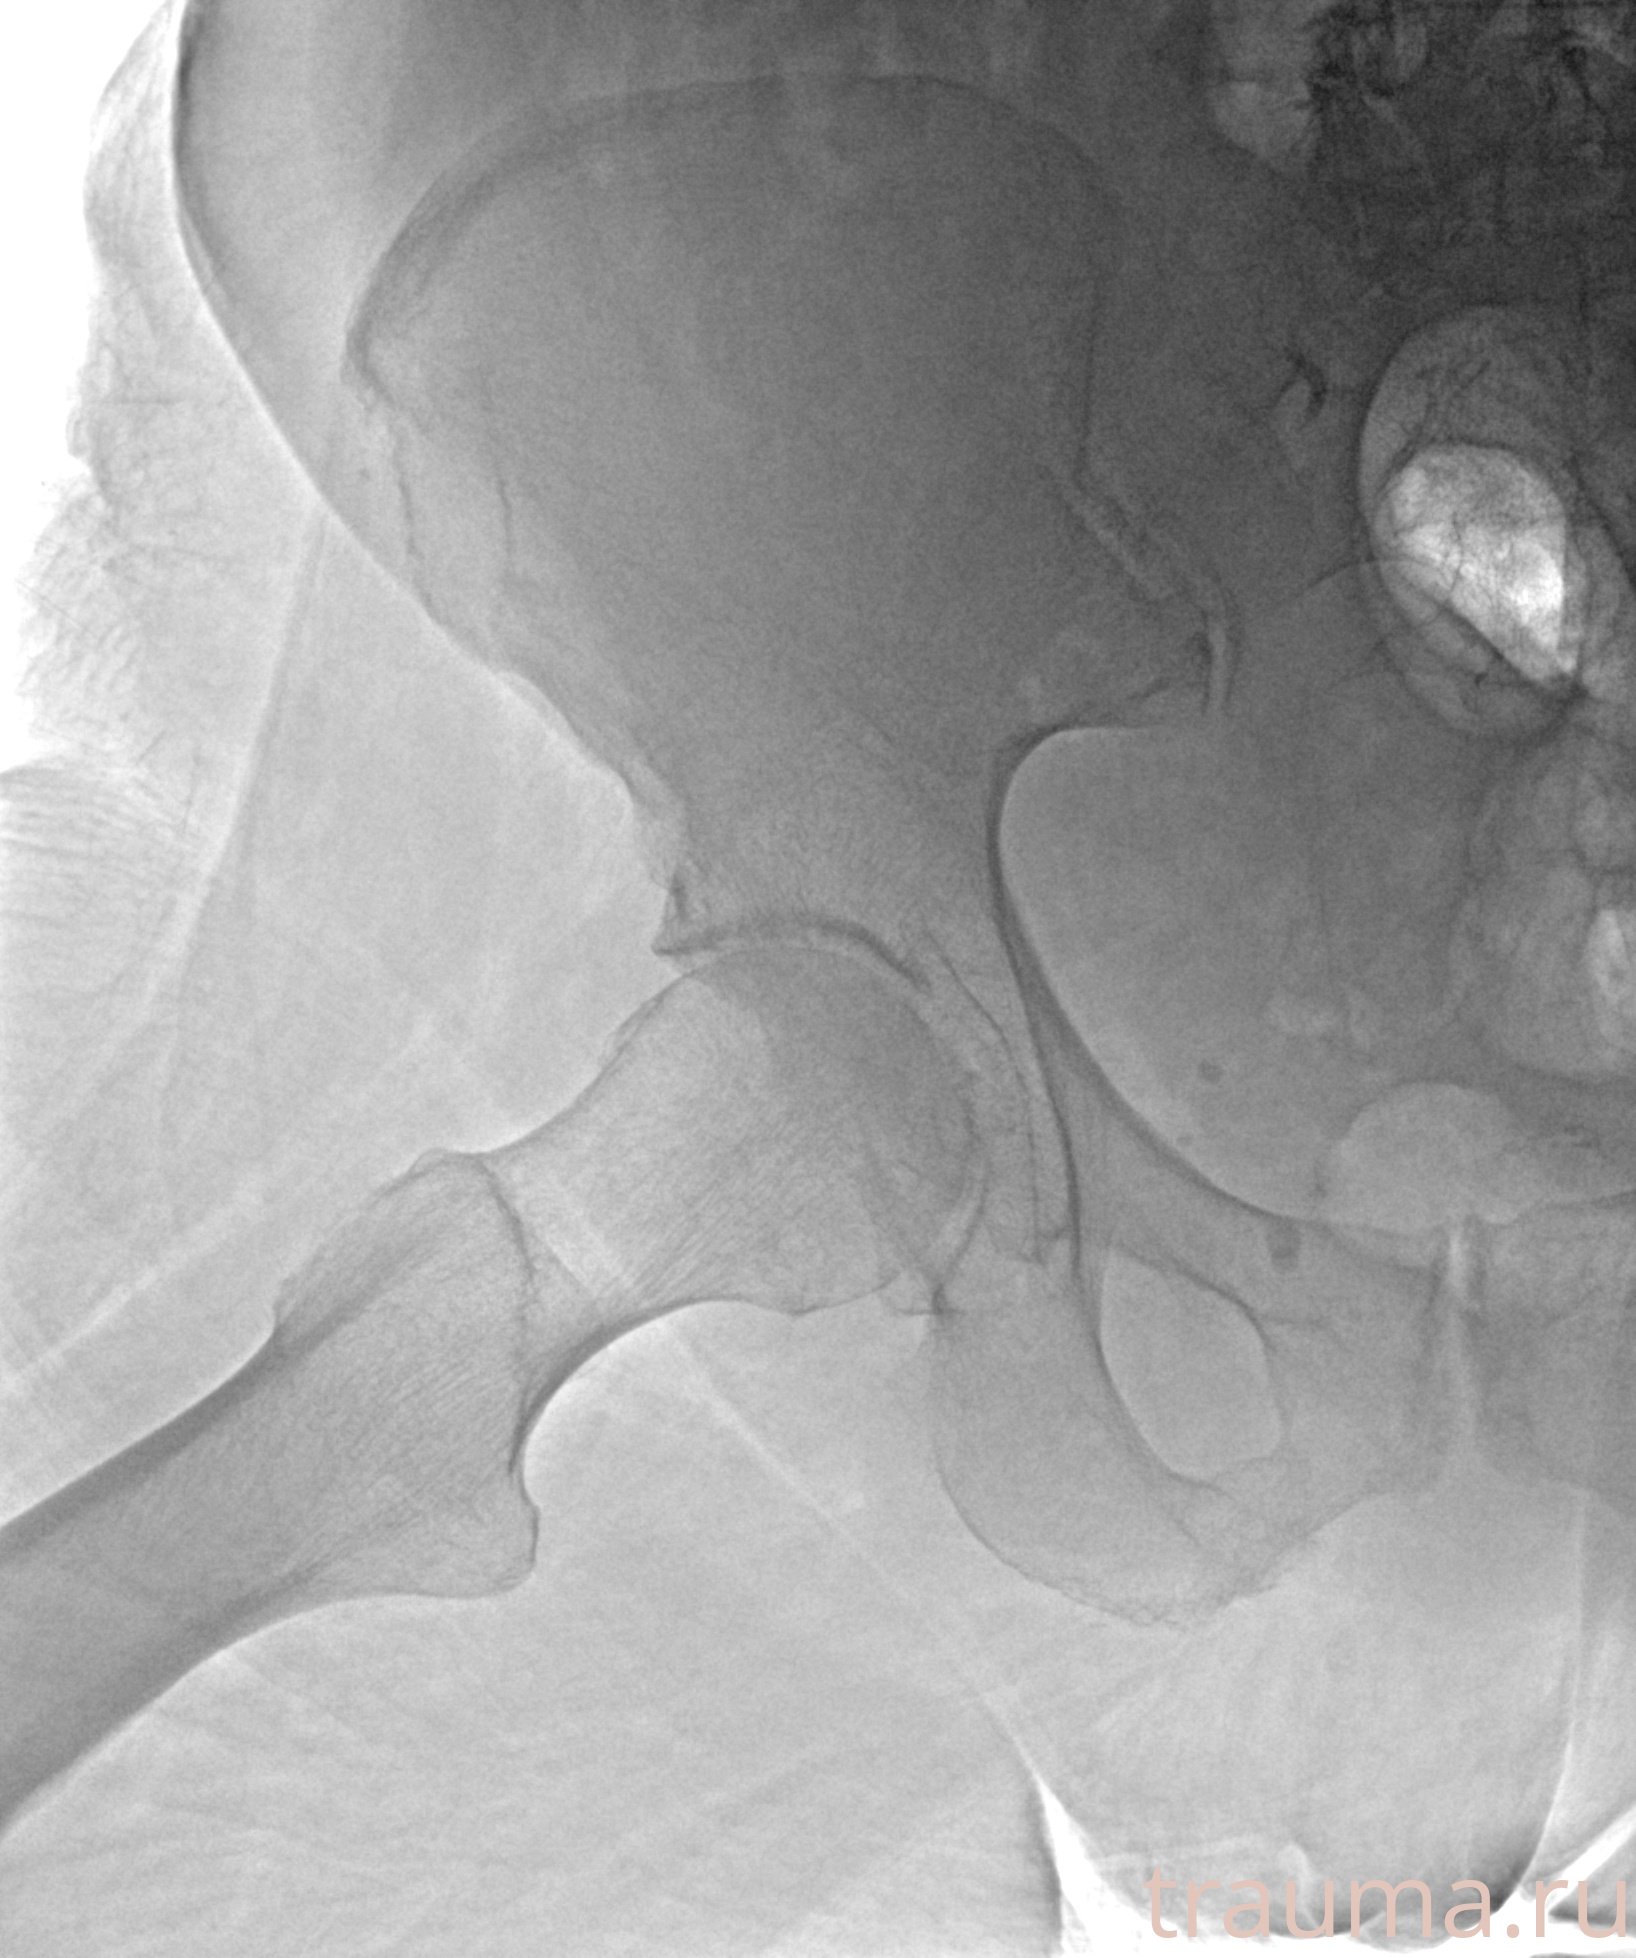

Рентгенограммы

Рентген на дому: по вашему адресу приезжает врач-рентгенолог, травматолог-ортопед с мобильным рентгеновским аппаратом, проводит диагностику травмы или заболевания, делает необходимые рентгенограммы, дает рекомендации по дальнейшему лечению. Получить качественные снимки в домашних условиях возможно благодаря уникальной методике, разработанной МосРентген Центром для института  Склифосовского